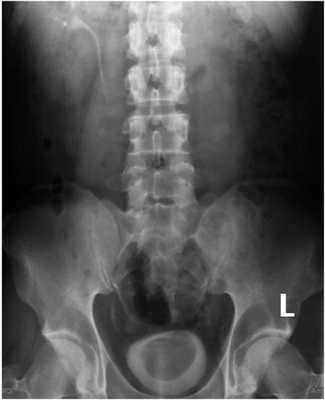

При компьютерной томографии (КТ) органов мочевыделительной системы диагноз агенезии правой почки был подтвержден, в проекции правого семенного пузырька выявлена киста диаметром 25 мм (рис. 5). Рисунок 5. КТ пациента В. Стрелкой указана киста семенного пузырька, пролабирующая в полость мочевого пузыря.